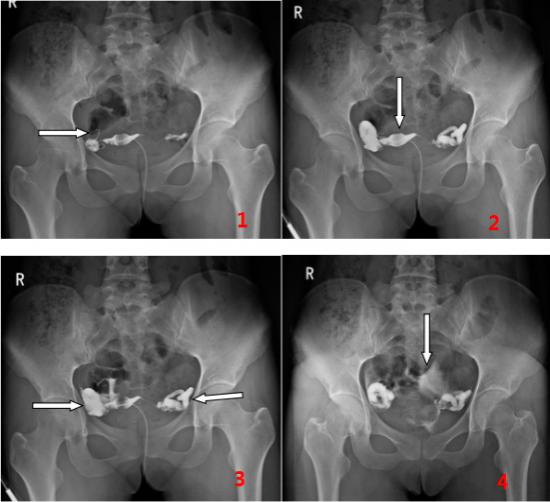

单某某、女、35岁,计划生育二胎未果,到医院检查,使用动态DR做子宫输卵管造影检查。检查过程中采用矩形数字化透视成像(43cm×43cm),观察造影剂流动情况,并对特征影像进行实时高清点片,获取900万像素影像如下:

图1、2清晰显示:左箭头示右侧输卵管迂曲,间质部、峡部通畅,显影良好;上箭头示子宫壁毛糙。图3、4可知:左、右箭头分别示右侧、左侧输卵管壶腹部和伞部积水扩张,右侧输卵管伞端部分造影剂流出,提示通而不畅;左侧输卵管未见明显造影剂流出,提示堵塞不通。上箭头示弥散至盆腔内的造影剂。综上所述,可以精准判定左侧输卵管堵塞。